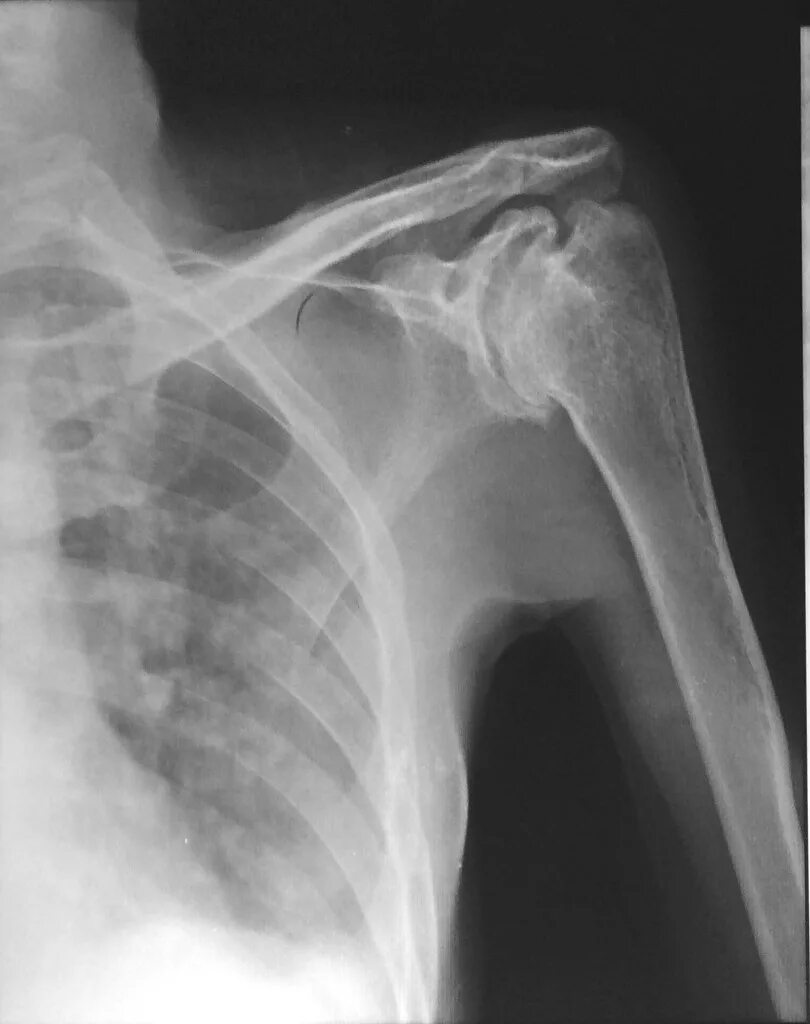

Туберкулез суставов симптомы